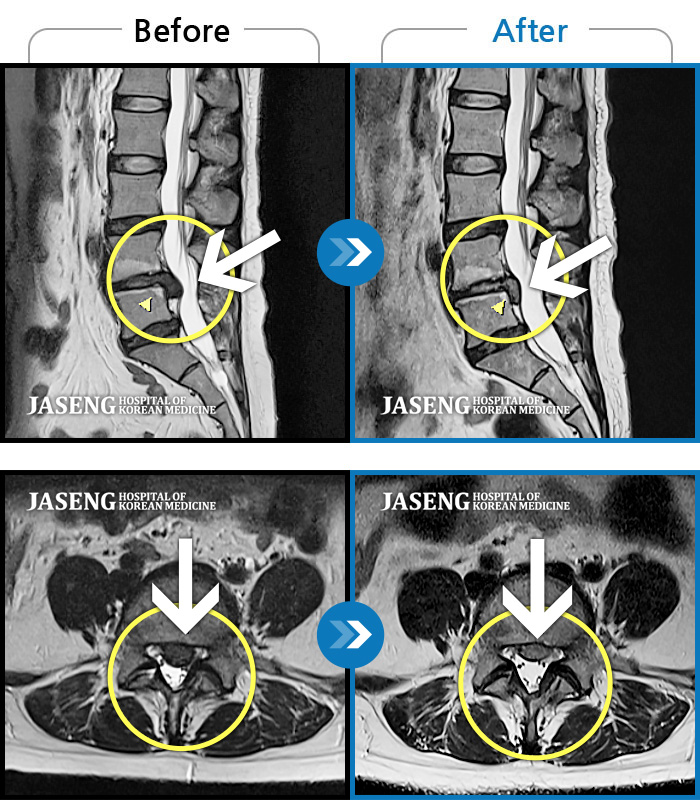

허리디스크

도움받은 사례

광주 · 장영우 원장

좌측 허리 통증으로 허리를 반듯이 펴고 서있기 힘들어 내원하셨습니다.

촬영시기

2024.08.12 ~ 2025.02.26

2025.03.07